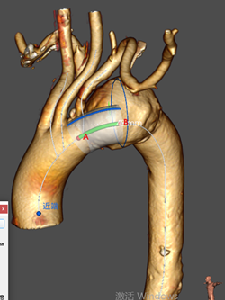

★ 病例4:主动脉夹层真腔狭窄

该病例主动脉弓部真腔严重狭窄受压,有可能影响主体支架的释放和寻找分支通道。

与主体支架一体化的无名动脉外分支和凹陷区域,留出空间用于置管和容纳单独的分支支架。手术操作简单,效果良好。